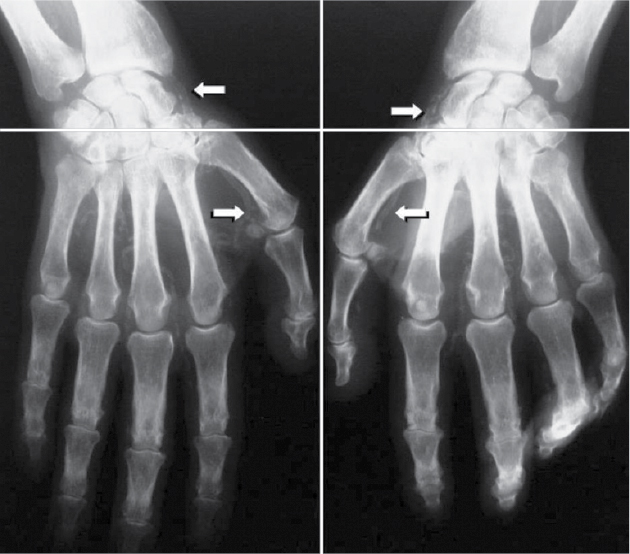

Adragao Score

This vascular calcification score was evaluated from bilateral iliac, femoral and radial arteries in plain radiographic films of pelvis and hands. The pelvis radiographic films were divided into four sections by two imaginary lines: a horizontal line over the upper limit of both femoral heads and a median vertical line over the vertebral column. The films of the hands were divided, for each hand, by a horizontal line over the upper limit of the metacarpal bones. The presence of linear calcifications in each section was counted as 1 and its absence as 0. The final score was the sum of all the sections, ranging from 0 to 8.18 Vascular calcifications were deliberately evaluated only in muscular arteries: iliac, femoral, radial and digital. Pelvic films evaluated iliac and femoral arteries (Fig. 1); wrist films evaluated radial and digital arteries (Fig. 2). Only linear calcifications, with or without patchy calcifications, were considered for the final calcification score, because they outline the vessel wall and have undoubtedly vascular localization. Patchy isolated calcifications that may be associated with intimal calcifications were not considered in this score.

Figure 2. Vascular calcification score - Wrist films to evaluate radial and digital arteries.

In this study, vascular calcifications were deliberately evaluated only in muscular arteries: iliac, femoral, radial and digital, because muscular arteries are more prone to linear calcification in contrast with elastic arteries that are more prone to intimal calcification. Vascular calcification causes arterial wall stiffness,19 which results in increased cardiac afterload leading to left ventricular hypertrophy. These functional and structural changes associated with vascular calcification have strong clinical impact on cardiovascular morbidity and mortality in dialysis patients. Also, if the prevalence of both vascular calcification and CVD is high in hemodialysis patients, the association between the two observations seems logical. Indeed, several observational studies confirmed this association, suggesting linear relationship between vascular calcification and cardiovascular morbidity and mortality.14,20-22